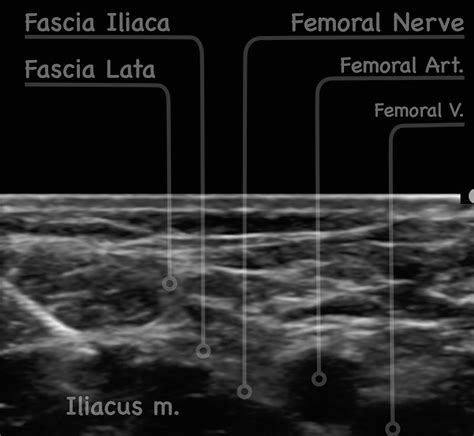

The ultrasound-guided approach provides real-time visualization of the needle and the target nerves, enhancing the precision and safety of the block. The steps are as follows:

1. Position the patient supine with the leg slightly externally rotated.

2. Place the ultrasound probe transversely over the inguinal region, just medial to the ASIS.

3. Identify the fascia iliaca, femoral nerve, and femoral artery.

4. Insert the needle in-plane with the ultrasound probe, aiming for the fascia iliaca.

5. Advance the needle until it reaches the fascia iliaca.

6. Aspirate to ensure no blood or cerebrospinal fluid is aspirated.

7. Inject the local anesthetic solution while visualizing the spread of the anesthetic under the fascia iliaca.